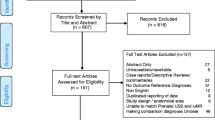

Studies were assessed for inclusion by two reviewers working independently and any disagreements were resolved by consensus. A PRISMA flow chart was completed detailing the selection process (Fig. 1).

The searches retrieved 818 studies which were reduced to 479 studies once duplicates were removed. Abstract screening reduced the number of studies to 41 studies which were assessed for eligibility. Following assessment, twelve studies were included in the final analysis. Details of the reasons for exclusion can be found in Fig. 1. PRISMA flow chart. All included studies compared the diagnosis made on ultrasound with a fetal MRI which was performed after the ultrasound anomaly had been detected. This process reflects clinical practice and allowed assessment of whether the MRI provided additional information which altered the management of the pregnancy.